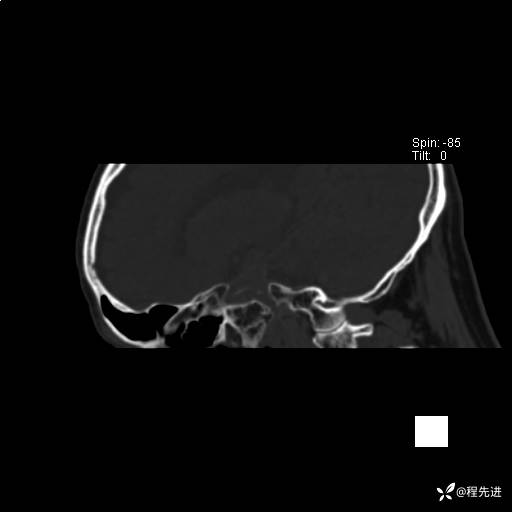

患者性别:男

患者年龄:74岁

简要病史:出现视物重影2月余,未予重视,2月来症状逐渐加重

实验室检查:无特殊

CT平扫: